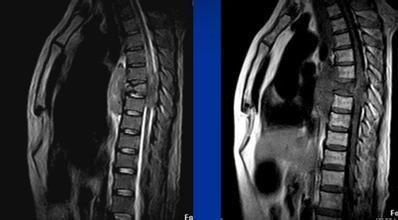

骨结核大多是由肺结核继发的。属于结核菌的隐匿性感染。结核菌核大多首先发生在肺部,在肺部感染后通过血液的传播可以到全身很多系统去,骨结核不是单纯的病变,是全身疾病在局部的表现。下面我们来学习一下有关骨结核病的知识。>>>不想看文章,直接咨询